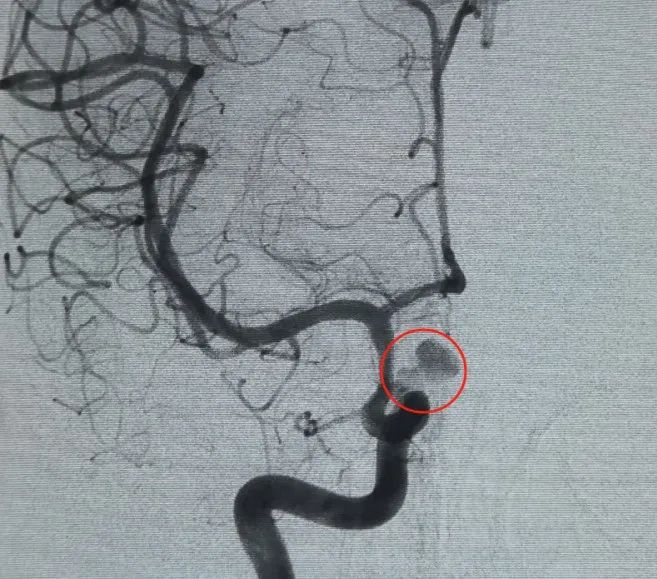

Diagnose: Aneurysma der linken inneren Hals schlag ader C6-Segment der Augen arterie

Ein Perfiller®3mm × 6 cm ausdehnbare Spule und ein Perfiller®3mm × 2 cm dehnbare Spule wurden dann platziert, um den Hals verschluss abzuschließen. Anschließend wurde ein Nuva®Der Durchfluss diverter (TJED-D. 0-16) wurde abgegeben und über den Aneurysma hals eingesetzt. Die Follow-up-Angiographie sowohl in antero posterioren als auch in lateraler Sicht bestätigte eine hervorragende Abdeckung, eine gute Wand zuführung und eine klare Strahl kraft mit deutlicher Kontrasts tag nation.

Das Verfahren wurde reibungslos ohne Komplikationen abgeschlossen, und der Patient erholte sich ohne neuro logische Defizite.